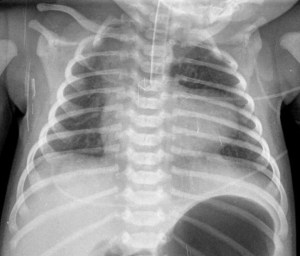

SIGNO DEL CORAZÓN EN FORMA DE MUÑECO DE NIEVE

El aspecto de muñeco de nieve que adopta la silueta cardiaca en la proyección antero-posterior de tórax es característica del drenaje venoso pulmonar anómalo total. La porción inferior del muñeco corresponde al crecimiento de la aurícula y el ventrículo derechos, y la superior corresponde a la vena anómala que alcanza la vena cava superior.